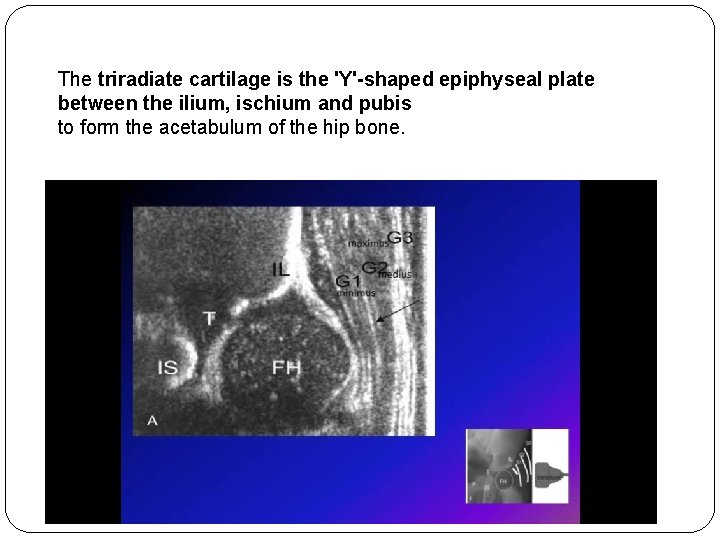

The triradiate cartilage is the 'Y'-shaped epiphyseal plate between the ilium, ischium and pubis to form the acetabulum of the hip bone.